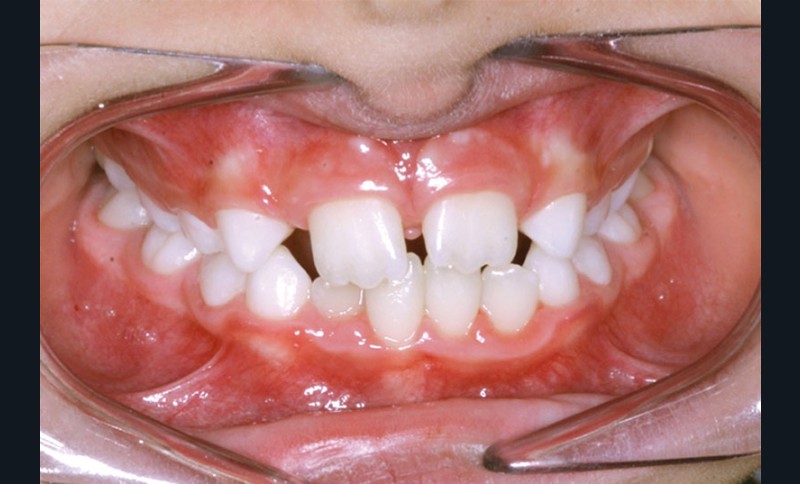

La décision thérapeutique s’est orientée dès cette consultation vers la fermeture des espaces d’agénésie et l’extraction de la 52 a été réalisée à ce stade pour respecter la symétrie antérieure et favoriser l’évolution symétrique des deux canines en position d’incisives latérales.

Les vues endo-buccales après extraction de 52 montrent des relations occlusales de classe II, un léger encombrement incisif mandibulaire et une tendance à la fermeture spontanée des espaces des incisives latérales confirmant le choix thérapeutique d’une fermeture d’espace (fig. 2).